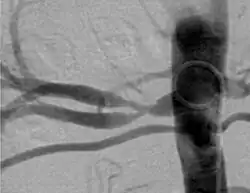

Wszystkie trzy typy mogą występować samodzielnie albo łącznie u jednego pacjenta. Klasyfikacja angiograficzna wyróżnia typ wieloogniskowy (multifocal type), z licznymi zwężeniami i obrazem „sznura pereł”, któremu w klasyfikacji histologicznej odpowiada typ z zajęciem błony wewnętrznej, typ cewkowy i typ ogniskowy, nie pokrywające się z klasyfikacją histologiczną.

| Klasyfikacja angiograficzna FMD | |||

|---|---|---|---|

| Typ I | Typ wieloogniskowy (multifocal type) | 62%[15] | ![]() |

| Typ II | Typ cewkowy (tubular type) | 14%[15] | ![]() |

| Typ III | Typ ogniskowy (focal type) | 7%[15] | ![]() |